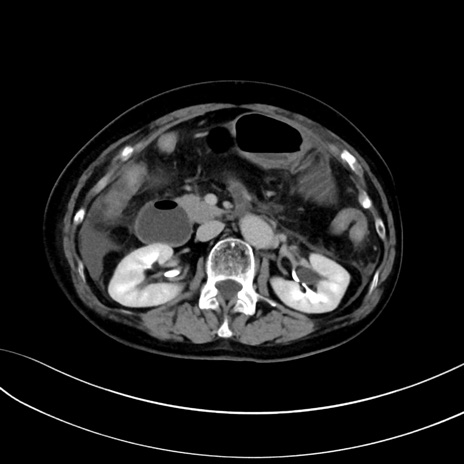

症例13 CT(横断像)1日半後